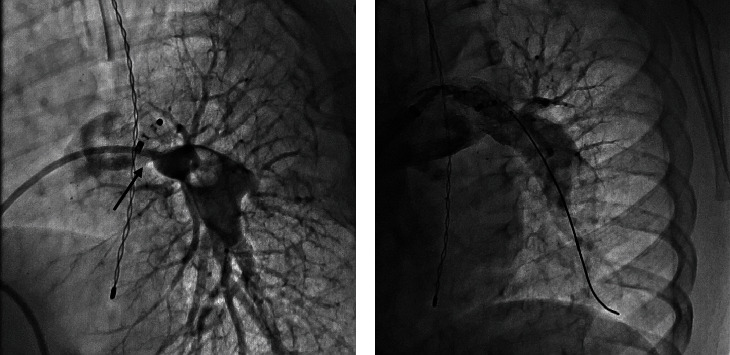

Percutaneous device occlusion is currently the standard of care for most cases of patent ductus arteriosus (PDA). Albeit infrequent, device-related left pulmonary artery (LPA) stenosis is a known complication of this procedure, occasionally requiring stent placement to relieve the obstruction. We present a series of four patients who required left pulmonary stenting after ductus arteriosus device closure. A review of the current evidence is presented.

Abstract Image